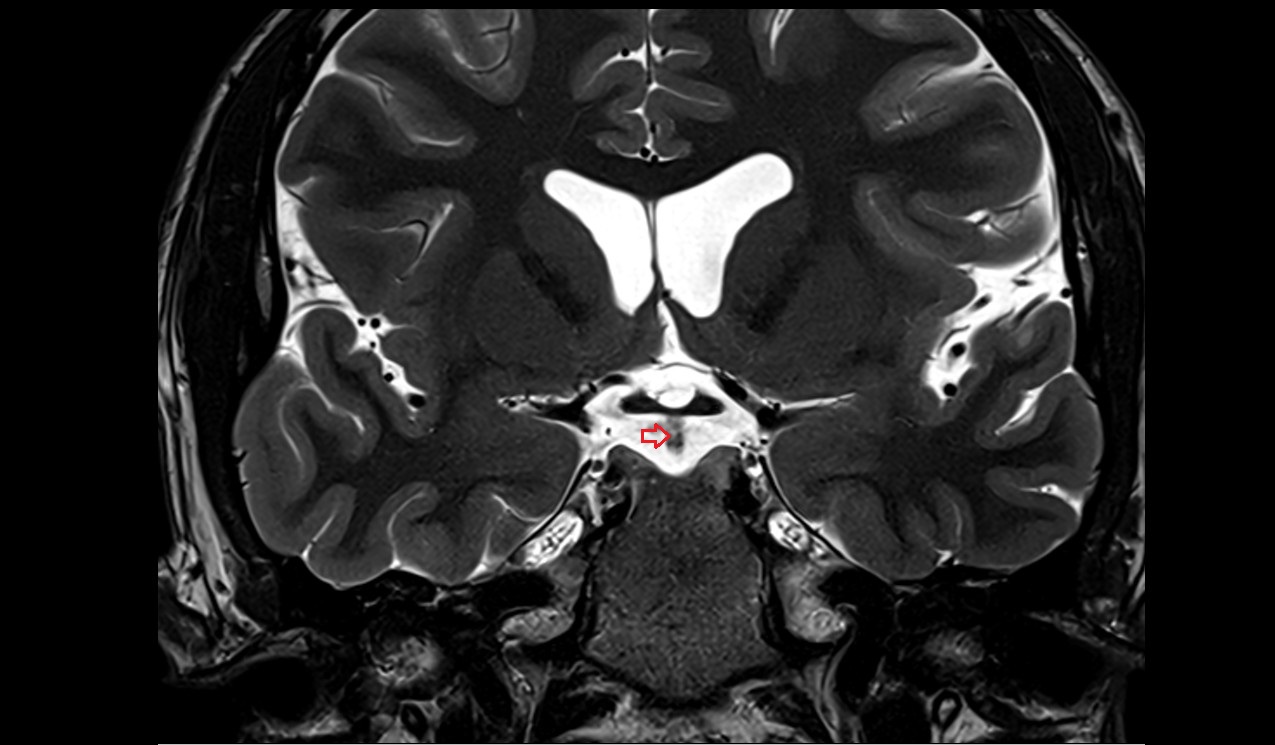

- Meckel’s cave (Trigeminal cave)